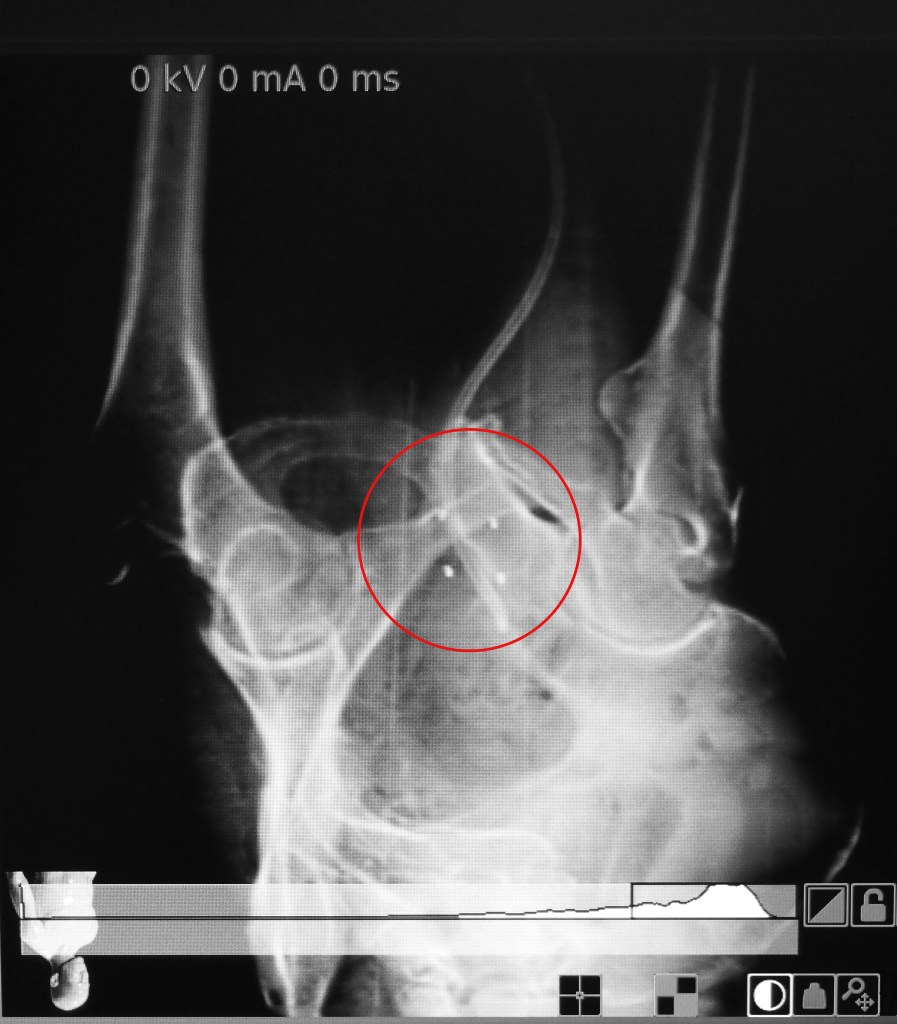

I next was moved by wheel chair to the CT imaging room. There the position of the fiducials and Spacer OAR was quickly scanned. Dr. C deemed the placement of the 4 fiducials as excellent. These fiducials will serve as permanent internal markers for the positioning of the Cyberknife, assuring that each treatment session is identical to the prior session. . The X-ray image shows the 4 fiducials (circled in red) as they were placed in my prostate on 5/10. I left the Cyberknife facility and treated myself to a lunch of Gulf oysters on the half shell and a cup of seafood gumbo on the way back to my residence. The balance of the day was spent with some business paperwork, then a light dinner, shower and early to bed about 9:00 PM.